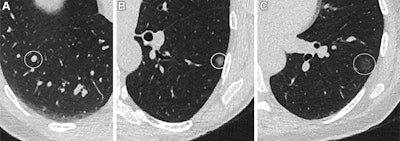

Transverse CT images show (A) a 120-mm3 solid pulmonary nodule, marked with a circle, in the right lower lobe in a 65-year-old male; (B) a 9-mm subsolid (part solid) nodule, marked with a circle, in the left lower lobe of a 57-year-old female; and (C) a 10-mm ground-glass nodule, marked with a circle, in the left lower lobe in a 52-year-old female.RSNA

Final analysis included data collected from 29,574 study participants with a median age of 57.4 years. The researchers found solid nodules sized 100 mm3 to 300 mm3 in 1,420 participants, part-solid nodules in 199 participants, and ground-glass nodules in 430 participants.